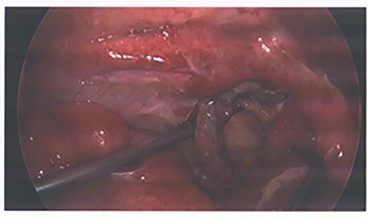

Due to the embolization of an end artery, the high possibility of ischaemia of the appendix was a concern and the patient was closely monitored for signs of rebleeding and peritonism. He was also prophylactically placed on IV antibiotics per trust guidelines for intra-abdominal pathology. After 72 hours of conservative management, he exhibited signs of local peritonism in the right iliac fossa and a rising white cell count and the decision was made to proceed with operative management. A laparoscopic appendicecetomy was performed, and he was found to have an inflamed appendix with blue discoloration indicating ischemia (Fig. 3). No perforation or other abnormalities throughout the examined bowel were identified. Final histology demonstrated partial distal infarction, healthy viable base and no sign of neoplasm. The patient had an unremarkable recovery following his operation and was discharged after 2 days.